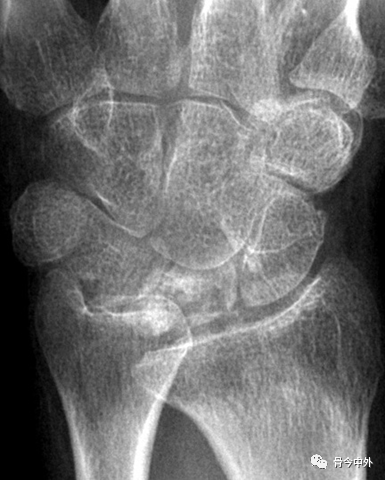

CASE 5:

图37

1.月骨-三角骨间隙平行关系缺失致掌骨弧线Iand II中断。

2.月骨和舟骨平行,而与其他腕骨不平行。

3.舟骨缩短提示向掌侧倾斜。

4.月骨平行于舟骨,其三角形状提示为掌侧倾斜所致。

5.近排腕骨不是一个整体,因为弧线I中断。

图38 侧位显示月骨向掌侧倾斜

最后诊断:掌屈不稳伴月骨-三角骨关节脱位。